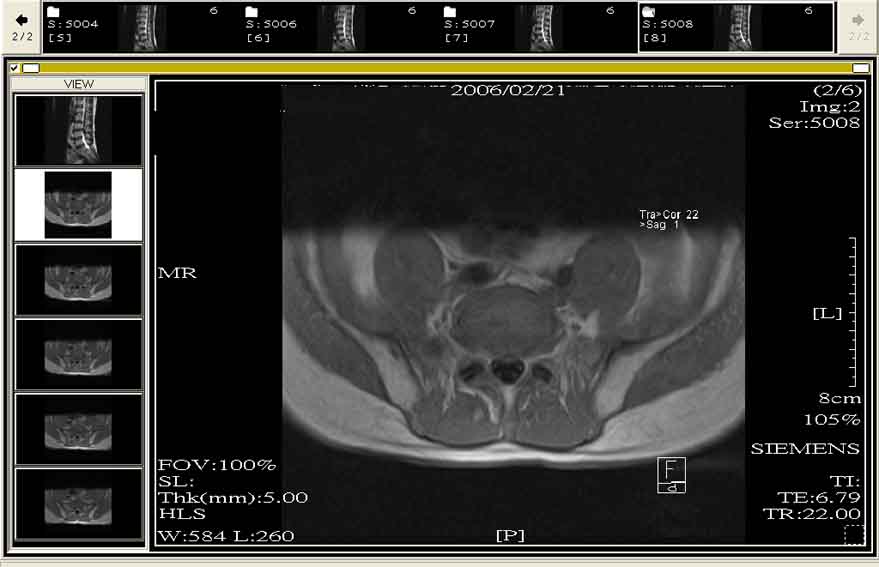

看片子在3-4節有椎間盤凸出現象

但就一張不容易判斷左右

受影響的神經有腰椎神經第三或第四條(對)

症狀是站立無力軟腿

但若出現大小變失禁

就要考慮是否是偏中央性凸出(看L3-L4的橫切圖會較清楚)

橫切面的圖

基本上應該可以看到他的編碼上有L3-L4

之類的

就是圖片裡面是一堆橢圓狀的

仔細看 應該有編號

豆仔:大大

很抱歉 找不到ㄋㄟ

只好貼一張橫切的

請多指教了!

附加檔案

1833508-P8A.jpg